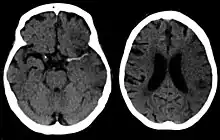

For diagnosing ischemic (blockage) stroke in the emergency setting:[64]

- MRI scan

- sensitivity= 83%

- specificity= 98%

For detecting chronic hemorrhages, MRI scan is more sensitive.[65]

CT scans may not detect an ischemic stroke, especially if it is small, of recent onset, or in the brainstem or cerebellum areas. A CT scan is more to rule out certain stroke mimics and detect bleeding.[9]